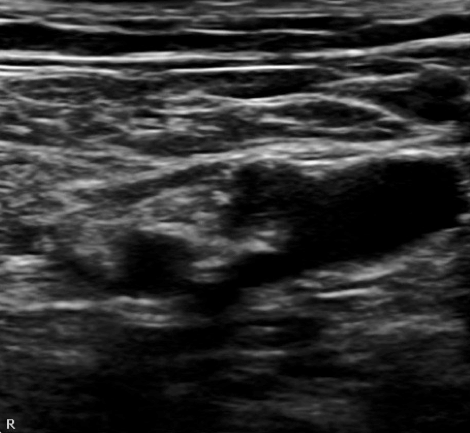

Reaching for their ultrasound machine and remembering the anatomy with the helpful pneumonic NAVEL (nerve, artery, vein, empty, lymphatics – from lateral to medial) the resident realizes that an ultrasound-guided femoral nerve block is just what the doctor ordered. The anatomy the physician identifies is pictured in Figure B (unlabeled) and Figure C (labeled). If done successfully, it could significantly decrease the patient’s pain score and eliminate the need for further parenteral opioid administration in this frail and elderly patient. Before proceeding, the physician ensures that the literature supports this ultrasound-guided emergency procedure.

Figure B: Unlabeled Ultrasound Depiction of the Femoral Nerve, Superficial Femoral Artery, Deep Femoral Artery, Femoral Vein and Fascia Lata. Lateral is depicted by the indicator mark P in the upper left corner of the image.

At the femoral crease, the nerve lies beneath the fascia lata and the fascia iliaca as depicted again in Figure B and C. The patient is placed into a supine position with slight abduction and slight Trendelenburg. The probe is placed along the femoral creases with the goal of locating the femoral artery. Following self-orientation, the probe is moved cephalad and caudad to further delineate the surrounding anatomy.

The nerve will appear as triangular in shape and should also be traced to confirm that it is not a lymph node. The nerve can be located above the bifurcation of the femoral artery (separating into the the superficial femoral artery and the deep femoral artery) or between the superficial femoral nerve and the deep femoral nerve as depicted in this case. Once the nerve location has been confirmed, the skin should be prepped. A local skin wheal can be made with a 27-gauge needle at the lateral aspect of the probe equidistant to the depth of the nerve. For instance if the nerve lies 2 cm deep, the anesthetic and needle entry should be 2 cm lateral to the probe indicator.